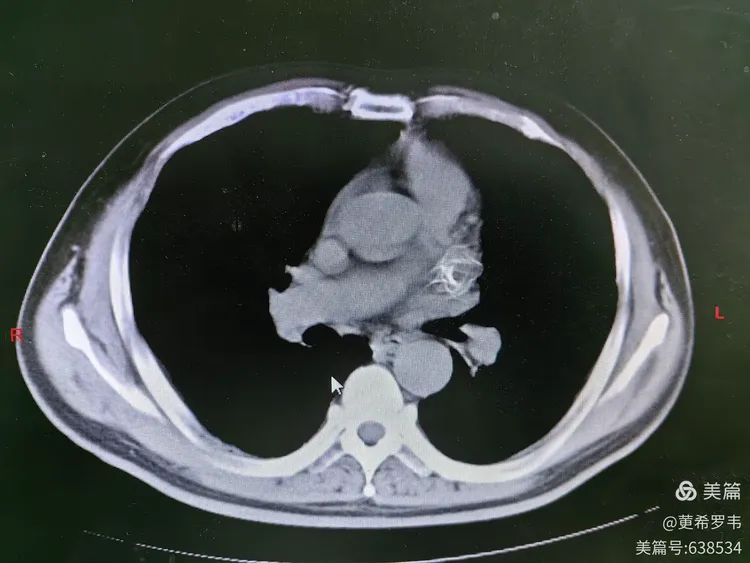

冠脉cta双房增大,二尖瓣轻度反流la 38mm,lvdd 50mm,ef 65%心

术前cta患者入院诊断及评分术者:燕翼 教授医院:广州医科大学附属第三

结合术前左心房增强ct影像学显示的左心耳解剖特点,团队最终决定应用